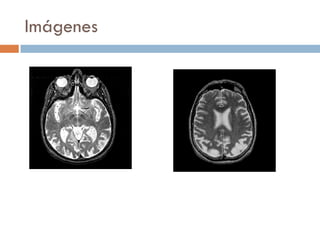

Imágenes atrofia temporal

medial

atrofia temporo-

parietal

atrofia difusa

Imágenes

Estadío 1 Estadío2 Estadío 3 Lenguaje anomias afasia fluente ecolalia mutismo Memoria episódica grad temporal reciente y remota compr global VE Dificultad copia estruct. simples dificultad copia estr. complejas compr severo Cálculo - alterado compr severo St. NPS depresión,apatía anosognosia, delirios Apatía, delirios,agitación St motores NO inquietud motora Imágenes atrofia temporal medial atrofia temporo- parietal atrofia difusa